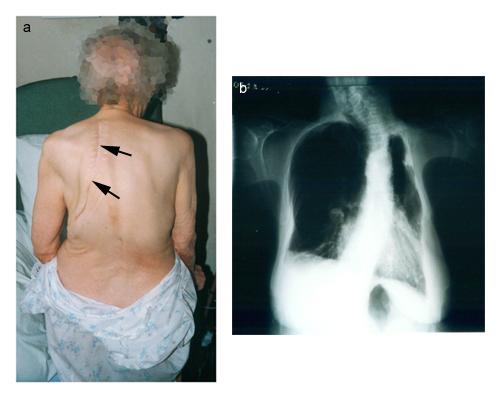

a) photographie de dos montrant une perte de volume du thorax du côté gauche avec une cicatrice de thoracoplastie (flèches)

b) radiographie montrant la perte de volume à gauche